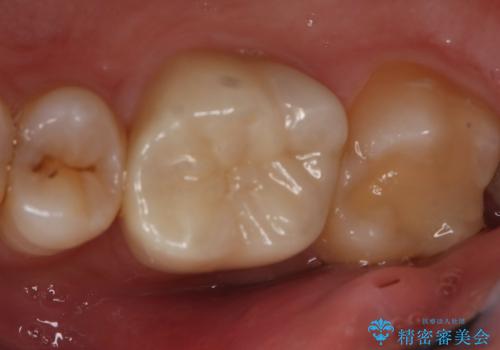

切削量などを考慮し、フルジルコニアクラウンでの治療を選択しました。

う蝕が深く切削量が多くなりましたが痛みなどは起きなかったので、予定通りフルジルコニアクラウンでの治療で進めました。